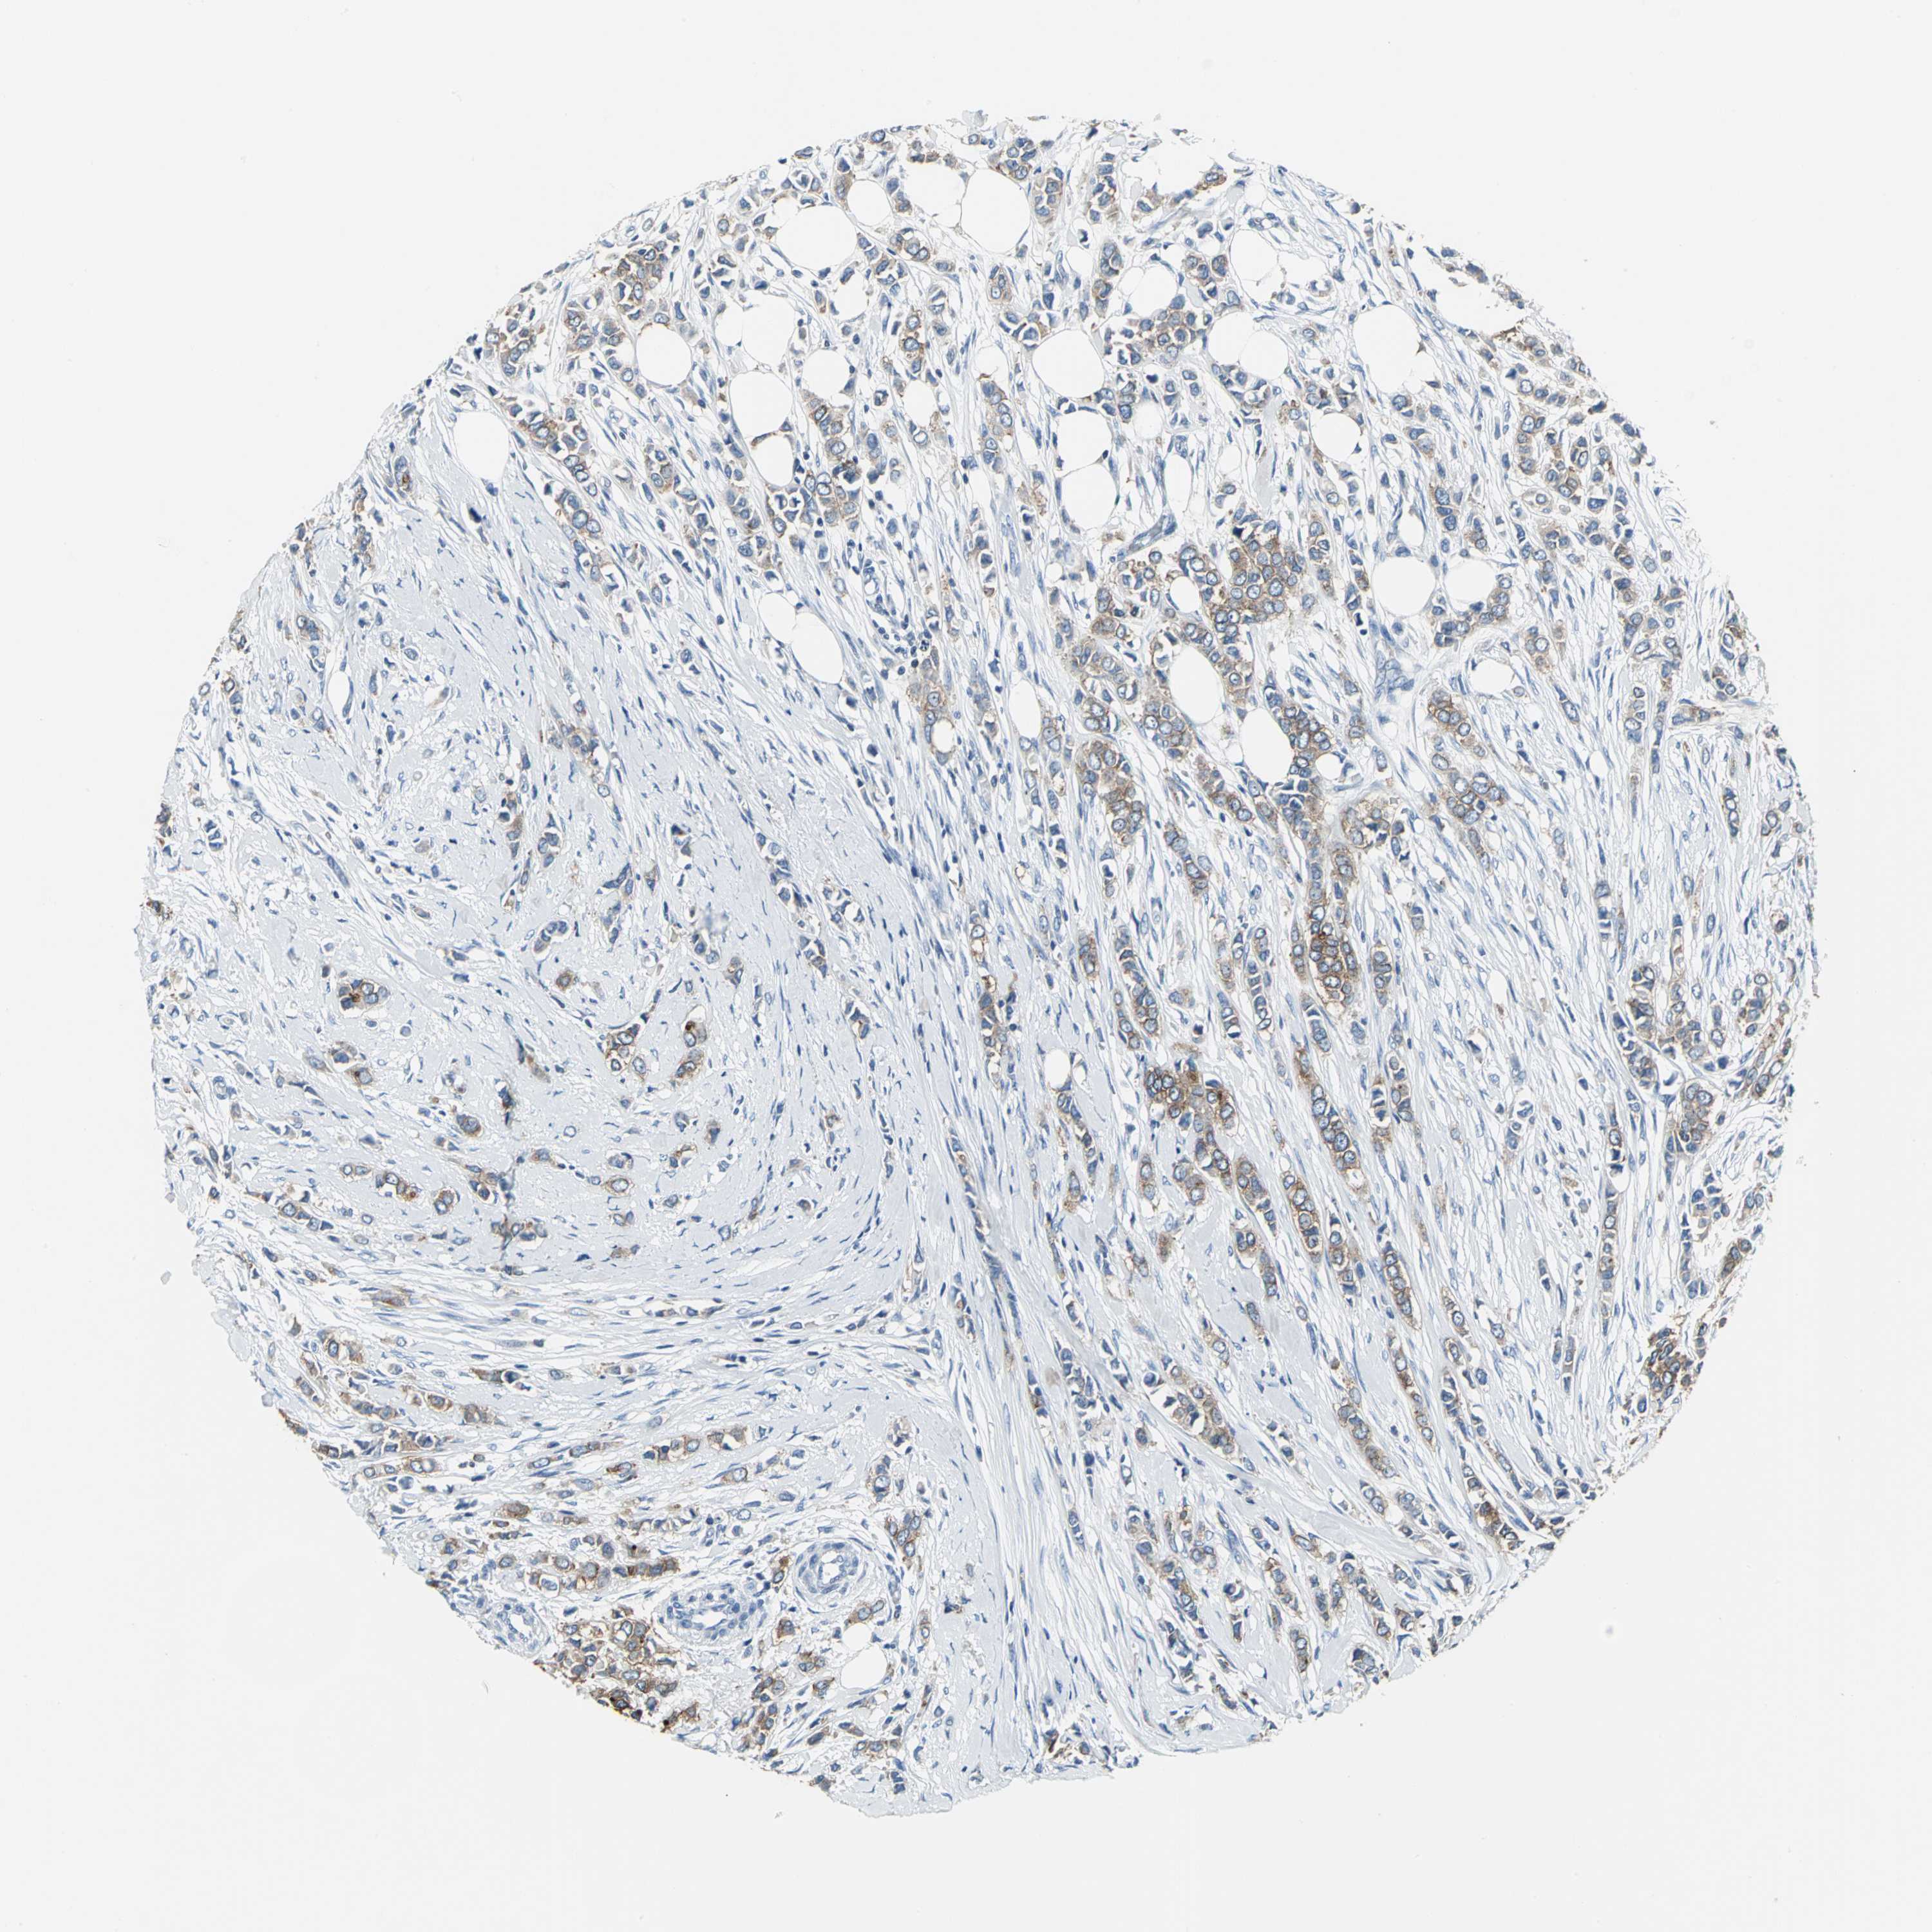

BRCA TCGA BRCA VALIDATION PROTEIN EXPRESSION